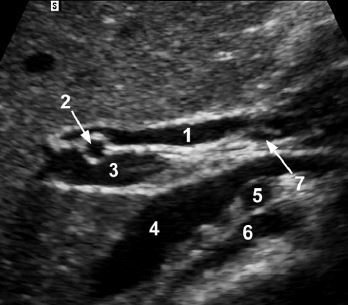

1. CBD

2. RIGHT hepatic artery

3. portal vein

4. IVC

5. right renal artery

6. right diaphragmatic crus

7. cystic duct insertion